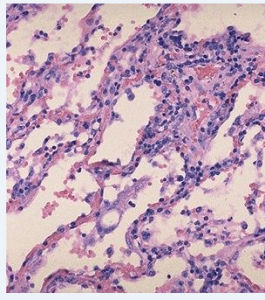

浸潤型肺結核原發感染經血行播散(隱蔽形成菌血症)而潛伏在肺內的結核菌多數逐漸死亡,僅當人體免疫力降低時,潛伏在病灶內的結合開始有機會繁殖,形成以滲出與細胞浸潤為主、伴有程度不同的乾酪樣病灶,稱為浸潤型肺結核(內源性感染)。原發病灶亦可能直接進展成浸潤型肺結核。

此外,與排菌肺結核患者密切接觸,反覆經呼吸道感染,亦可因再感染而法身浸潤型肺結核(外源性感染),但較少見,也不致發生菌血症。浸潤型和多未成年患者,起病緩慢,早期及病灶較小者,往往無明顯症狀及體徵,常由健康檢查或因其他原因作胸部X線檢查而發現。臨床症狀視其病灶範圍及人體反應性而定。病灶部位多在鎖骨上下,X線顯示為片狀、絮狀陰影,邊緣模糊。當人體處於過敏狀態,且有大量結合菌進入肺部時,病灶乾酪樣壞死、液化,進而形成空洞及病灶的支氣管播散。浸潤型肺結核伴大片乾酪樣壞死灶時,常呈急性進展,出現嚴重毒性症狀,臨床上稱為乾酪樣(或結核性)肺炎。乾酪樣壞死灶部分消散後,周圍形成纖維包膜;或空洞的引流支氣管阻塞,空洞內乾酪物難以排出,凝成球形病灶,稱“結核球”。

浸潤型肺結核浸潤性肺結核多見於曾受過結核感染的成年人。一般認為與原髮結核有密切關係,也可認為是原髮結核的發展後果。它是過去潛伏的、尚未癒合的原發病灶及早期血型播散病灶的重行活動引起的。只有少數人是因為與開放性肺結核病長期接觸而感染髮病(即外源性感染)。

浸潤性肺結核的病灶往往以肺尖及肺尖下部的浸潤,包括滲出性肺炎和灶邊反應開始。即使早期發現的病變,病灶雖然輕微,但往往已經發展到一定地步的乾酪樣變和纖維包圍,因此常見的早期病灶是程度不等的炎症浸潤和纖維結節的混合性病灶。病變有時自行癒合,病人毫無症狀,僅在檢查中發現肺尖部的結節病灶。根據人體的抵抗力及細菌的數量與毒力,浸潤性肺結核的炎症病灶可以通過滲出物的消散、吸收,結核結節的纖維化、玻璃樣變及乾酪樣變的纖維包圍、鈣化而趨於癒合;也可以發生乾酪樣壞死、液化、空洞形成和病灶的支氣管播散而發展惡化。病灶往往有好轉和不良發展同時存在,在炎症滲出成分消散的同時也可出現新鮮的炎症滲出病灶。結核結節也可以發生在壞死病灶的周圍,在X線上看來成為硬性的結節灶。